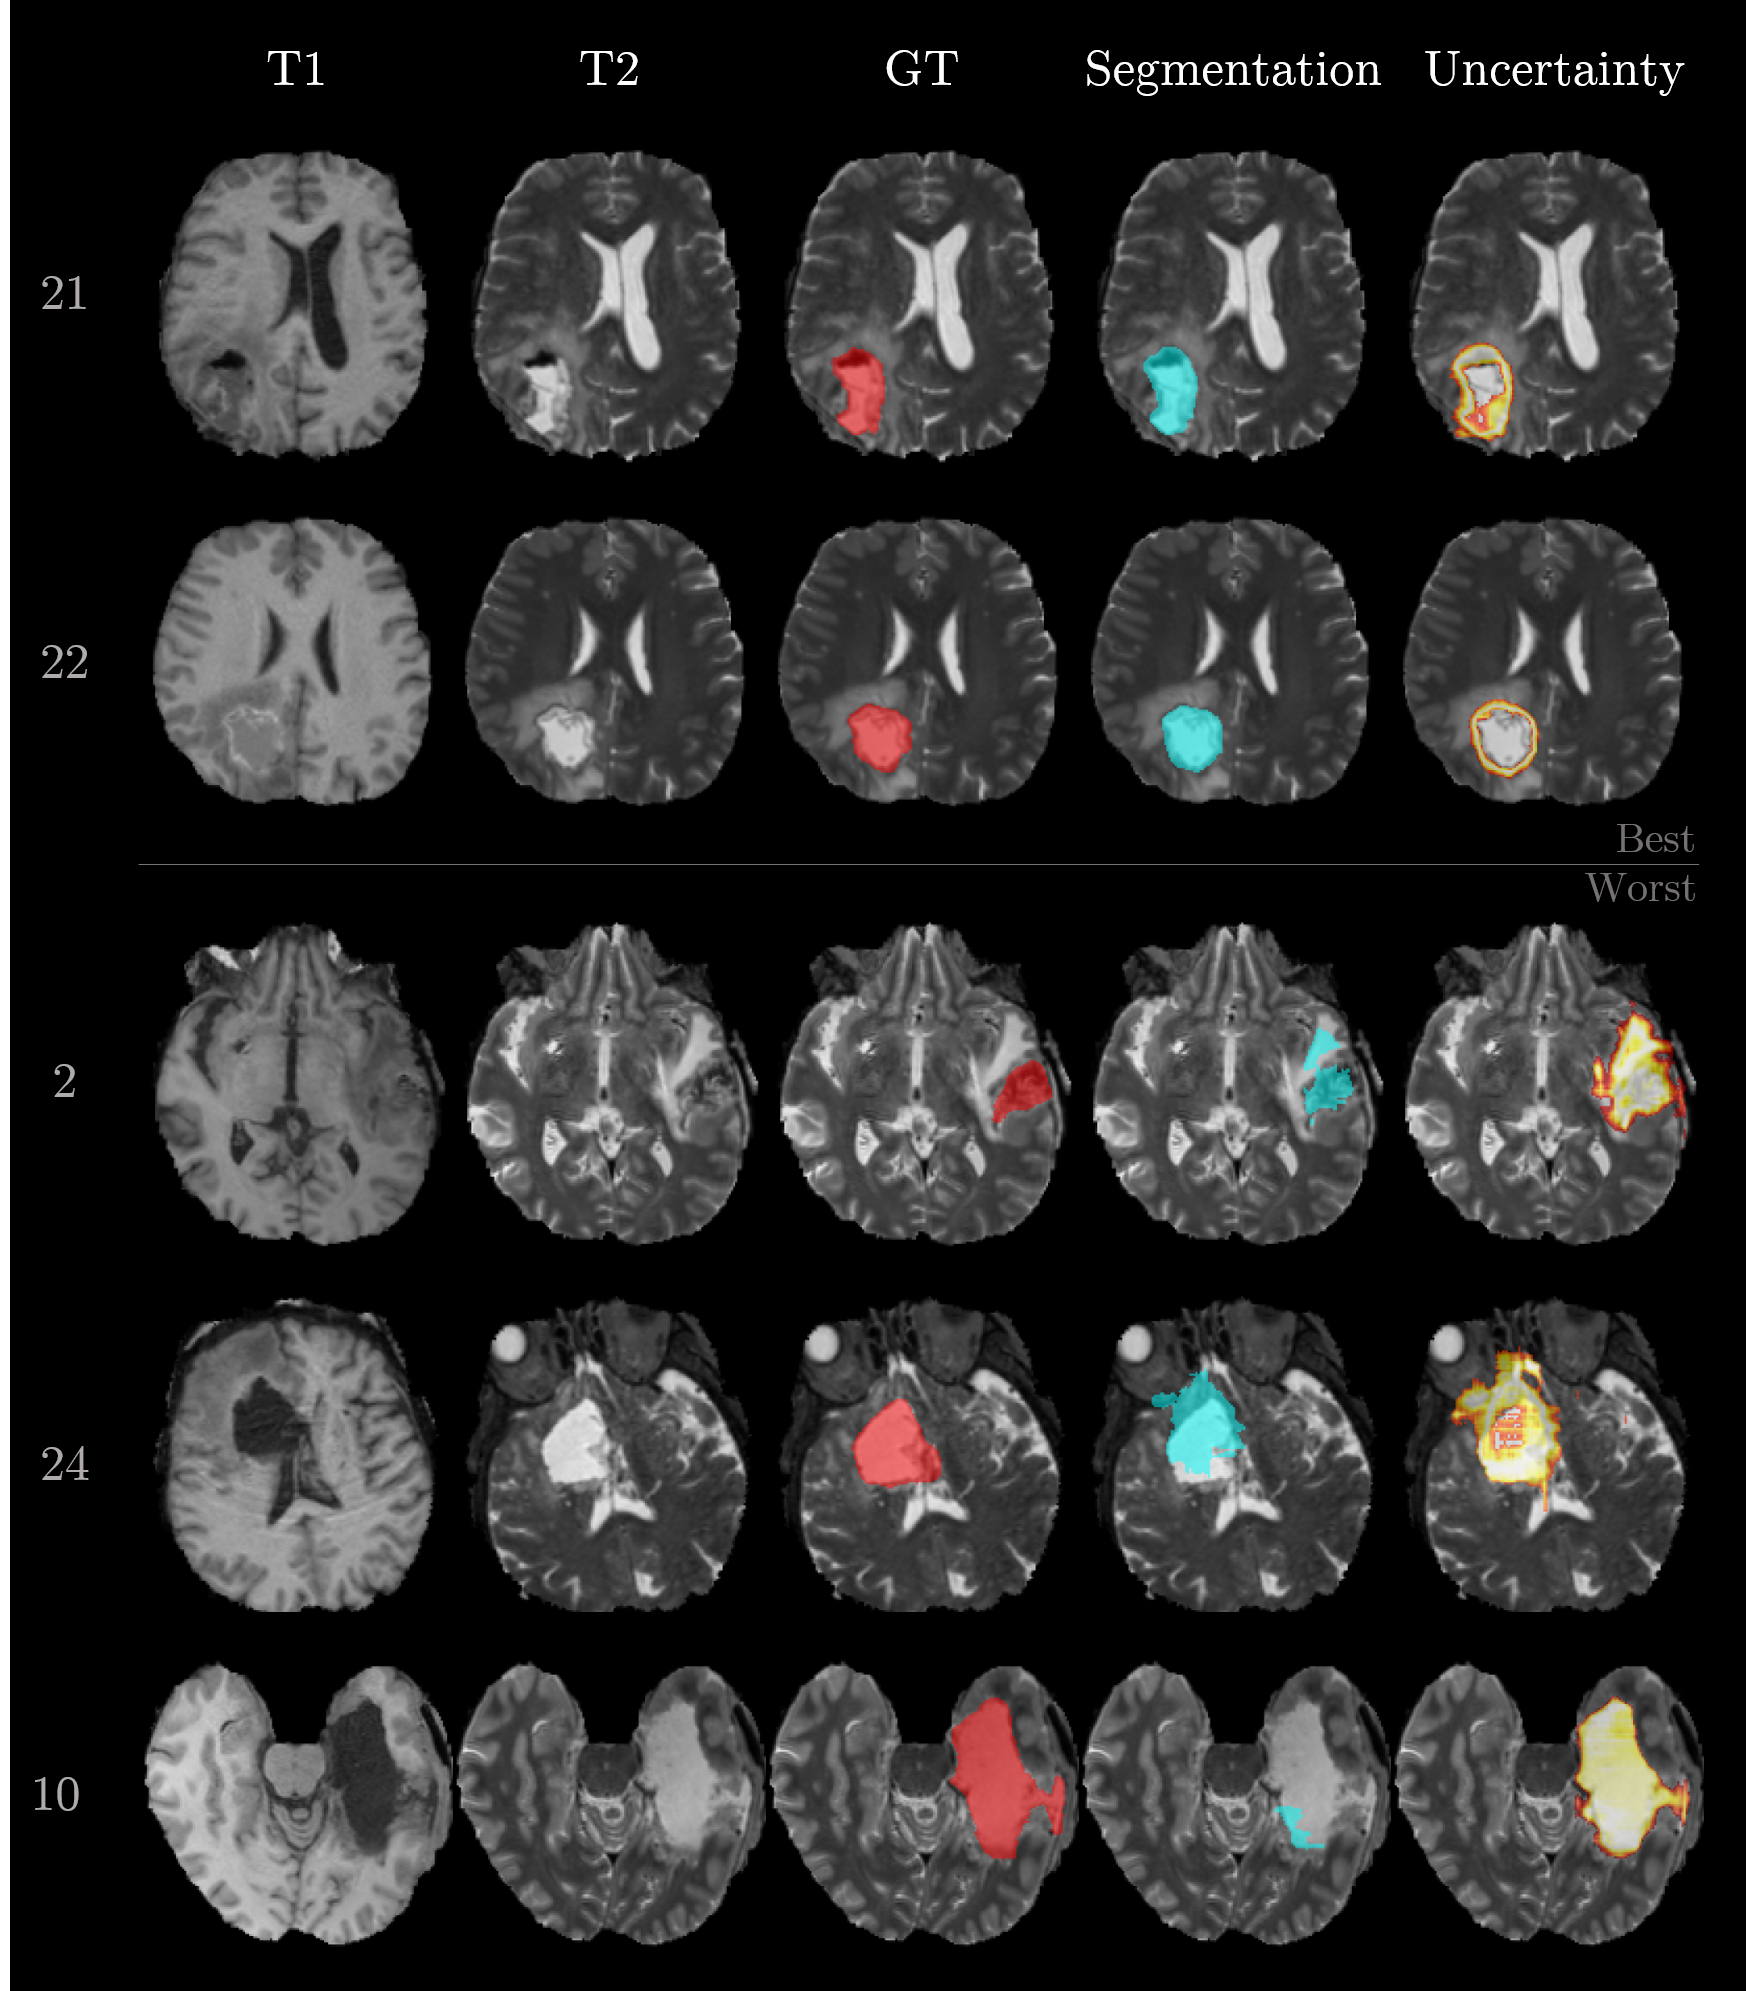

Figure 3 visualizes the segmentation results for the selected samples. The first and second row correspond to the best-performing cases. Their segmentation is close to ground truth and the uncertainty is mainly present at the boundary between foreground (i.e., cavity) and background. In contrast, samples 2, 24, and 10 show the worst performances. The network is struggling with the inhomogeneous cavity of sample 2. There is no clear delineation in the input sequences, which makes the task difficult. Sample 24 is most probably flawed because of the erroneous registration (compare T1 and T2 in Figure 3). Sample 10 is failing although the cavity is clearly visible in the T1 and T2 sequence. Further analysis of this case pointed to a particular hypointense cavity in the FLAIR sequence which appears isointense to cerebrospinal fluid and might confuse the network. Additionally, all three cases yielded increased uncertainties.